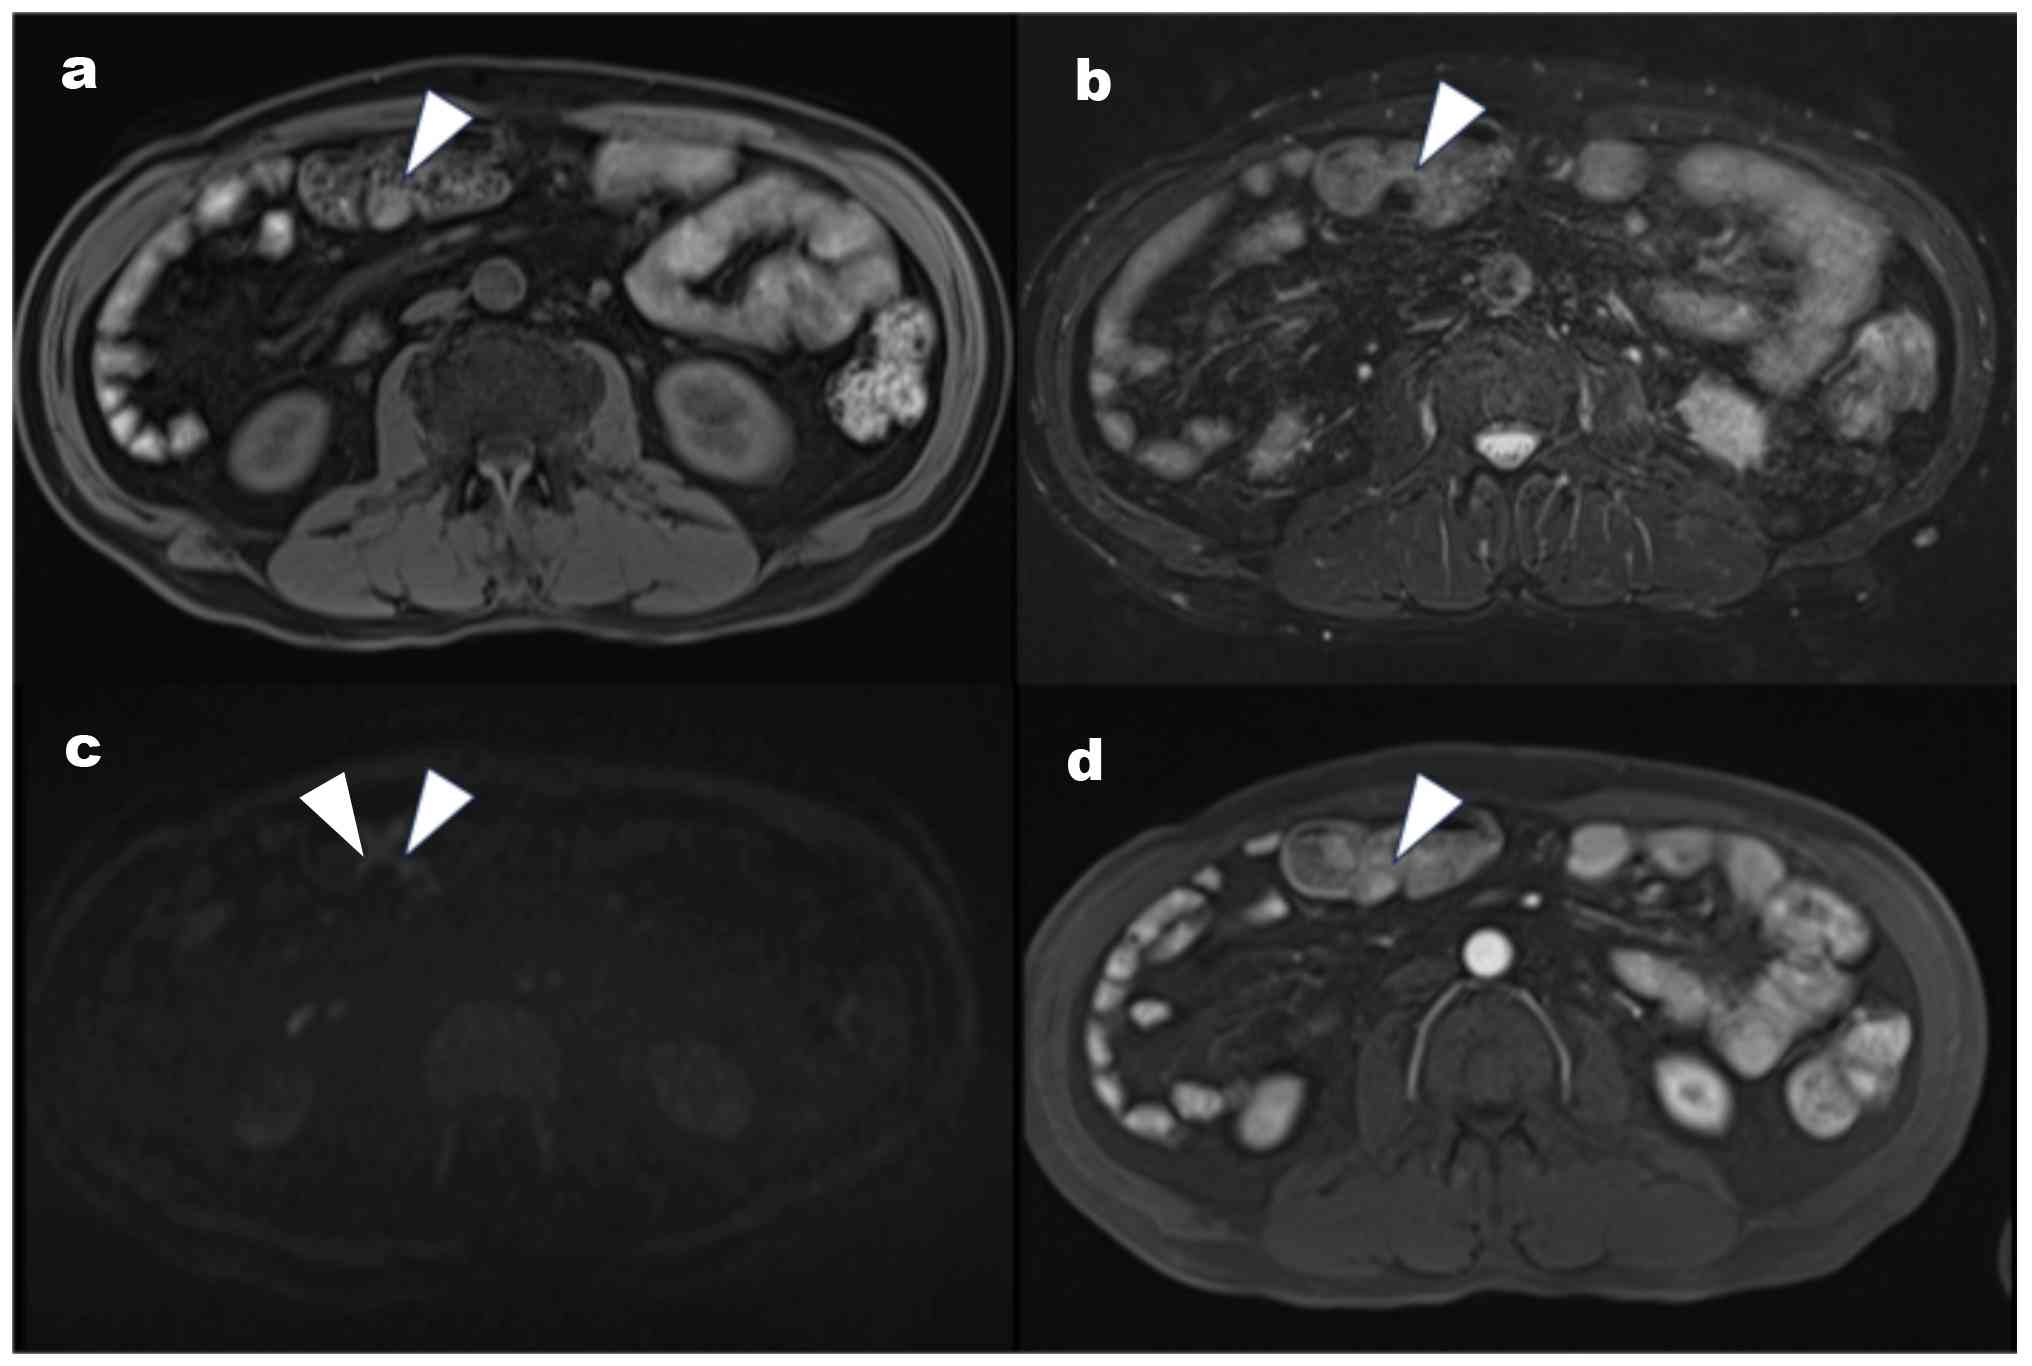

Contrast-enhanced MRI findings. MRI

showed a lesion (arrowhead) with (A) slightly high signal intensity

on T1-weighted imaging, but (B) without high signal intensity on

the T2-weighted imaging. (C) No apparent restricted diffusion was

observed (arrowhead) on diffusion-weighted imaging. (D) No obvious

contrast enhancement was observed (arrowhead) on the dynamic study.

MRI, magnetic resonance imaging.

Figure 2

Contrast-enhanced MRI findings. MRI showed a lesion (arrowhead) with (A) slightly high signal intensity on T1-weighted imaging, but (B) without high signal intensity on the T2-weighted imaging. (C) No apparent restricted diffusion was observed (arrowhead) on diffusion-weighted imaging. (D) No obvious contrast enhancement was observed (arrowhead) on the dynamic study. MRI, magnetic resonance imaging.